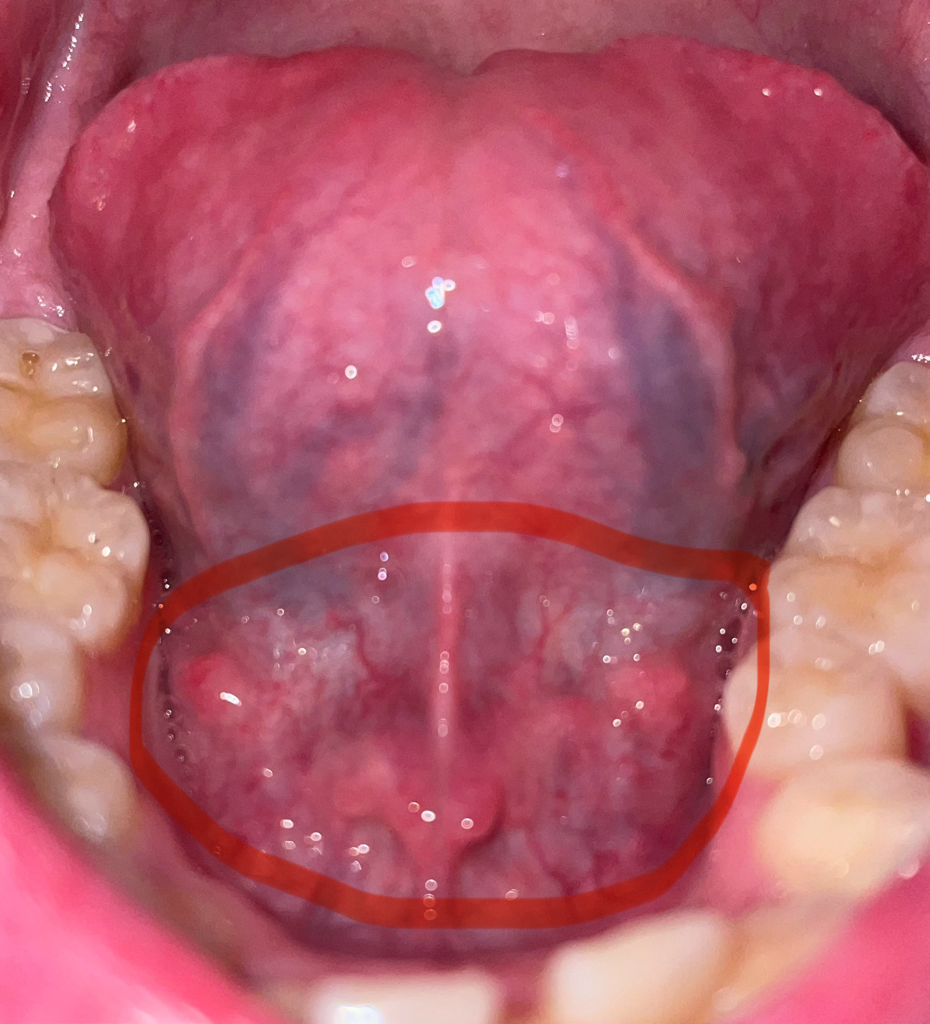

혓바닥 아래에 돌기같은것이 생겼습니다

동그라미 친 부분에

혓바닥 아래에 저렇게 볼록한것들이 생겼는데

저게 뭔가요? 아프지도 않고 아무 느낌 없기는 한데

괜히 신경 쓰입니다 혹시 문제가 있는걸까요?

안녕하세요. 이송재 의사입니다. 올려주신 사진으로 보았을 때 혀 아래쪽에는 특별히 이상이 있는 소견은 관찰 되지 않습니다. 현재 불편한 증상도 없기 때문에 지켜보시면 됩니다.